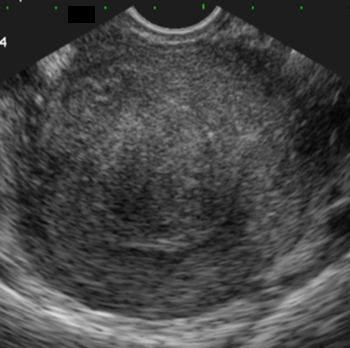

Myome sous-muqueux hypoéchogène par rapport à l’endomètre. Coupe transversale (Cliché : Dr. C. TALMANT)